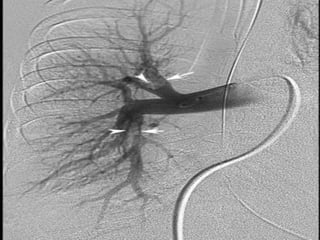

PulmonaryAngiogram-GoldStandard

• Pulmonary angiographyremainsthe accepted“gold standard” forPEdiagnosis.

• Onlytwo angiographicfindings arediagnosticof acute embolism:the filling defect

andabrupt cutoff ofavessel.

• Catheterisinserted in the right heart anddyeisinjected into pulmonary

trunk.

• Filling isobservedunderfluoroscopy.

• Limitations of PulmonaryAngiogram:

• It requires expertise in study performanceandinterpretation;

• it isinvasive.

• Highmortality due to procedureitself.

PulmonaryAngiogram-GoldStandard • Pulmonary angiographyremainstheaccepted“gold standard” forPEdiagnosis. • Onlytwo angiographicfindings arediagnosticof acute embolism:the filling defect andabrupt cutoff ofavessel. • Catheterisinserted in the right heart anddyeisinjected into pulmonary trunk. • Filling isobservedunderfluoroscopy. • Limitations of PulmonaryAngiogram: • It requires expertise in study performanceandinterpretation; • it isinvasive. • Highmortality due to procedureitself.